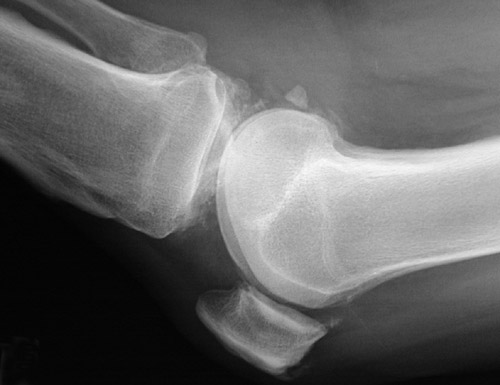

![]() | This series of knee radiographs reveals extensive chondrocalcinosis involving the menisci and articular cartilage. Note particularly the chondrocalcinosis of the meniscus above. Chondrocalcinosis is a condition related most to aging with calcium pyrophosphate dihydrate (CPPD) crystal deposition. The relationship to osteoarthritis is not clear, but CPPD disease can contribute to osteoarthritic changes, which are also present in these radiographic views. In the case shown here, bone density is not decreased. |